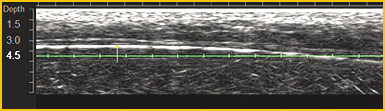

通过已获得专利的超声波影像技术,施术院长可以直接通过肉眼确认患密集的皮肤状态.

同时可避开骨骼及血管等敏感位置,将痛症和淤青降低到最小化.

施术时可通过实时超声波影像,确定骨骼和血管位置,可避免浮肿、痛症最小化.